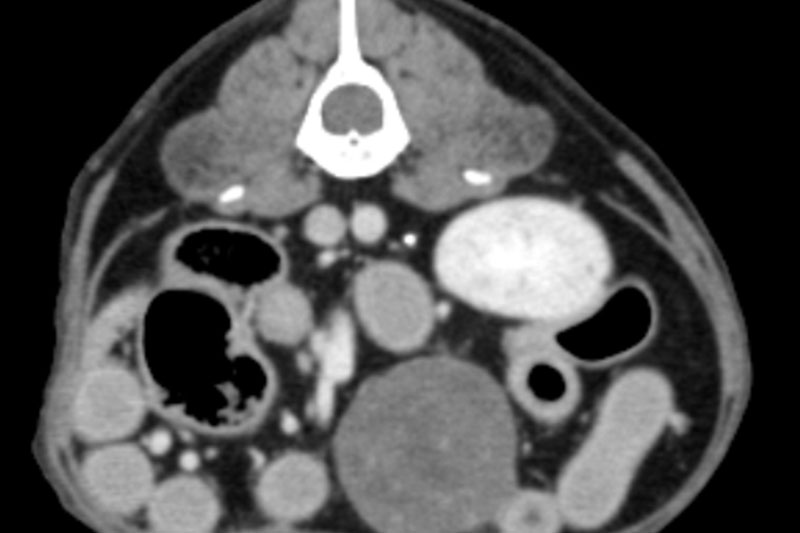

| 복부 | 간, 비장, 신장, 위장관 종양 및 결석, 부신, 림프절 등 |